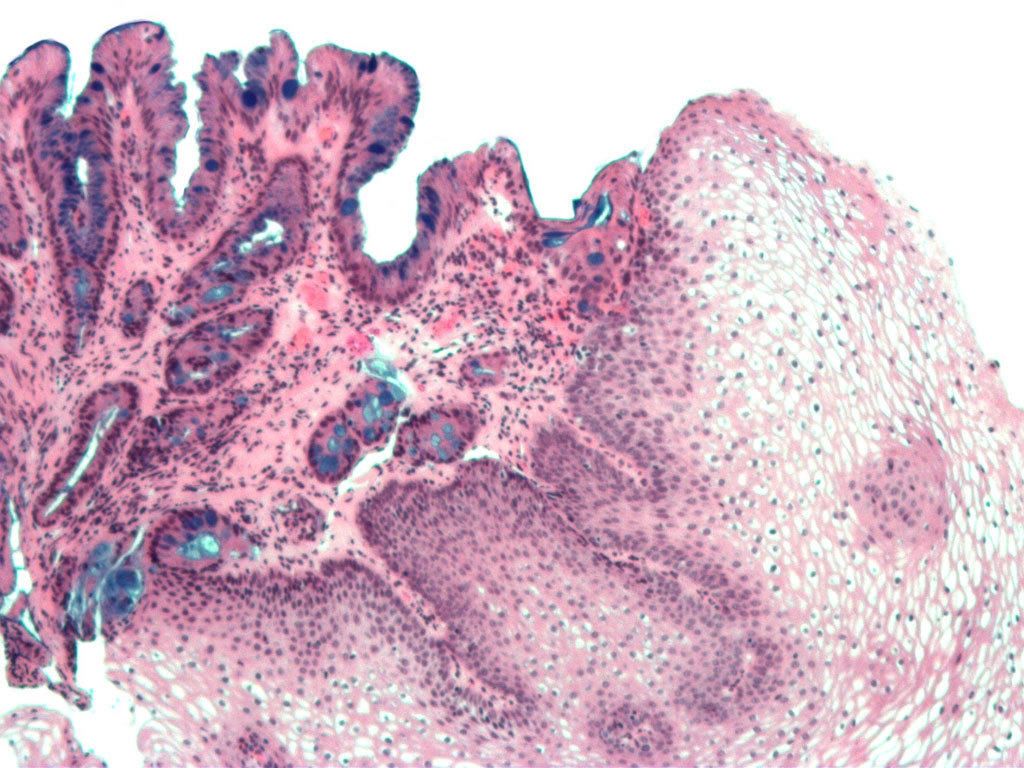

Bác sĩ thường chuẩn đoán bệnh thông qua nội soi thực quản bằng cách đặt một ống có gắn đèn vào miệng và đưa xuống thực quản. Sau đó, bác sĩ cũng có thể sử dụng phương pháp sinh thiết để kiểm tra các bất thường ở thực quản bằng cách lấy một mẫu mô nhỏ kiểm tra dưới kính hiển vi.

- Cách duy nhất để chẩn đoán bệnh là nội soi thực quản sau đó tiến hành sinh thiết mô. Bác sĩ chuyên khoa tiêu hóa sẽ tiến hành việc này;